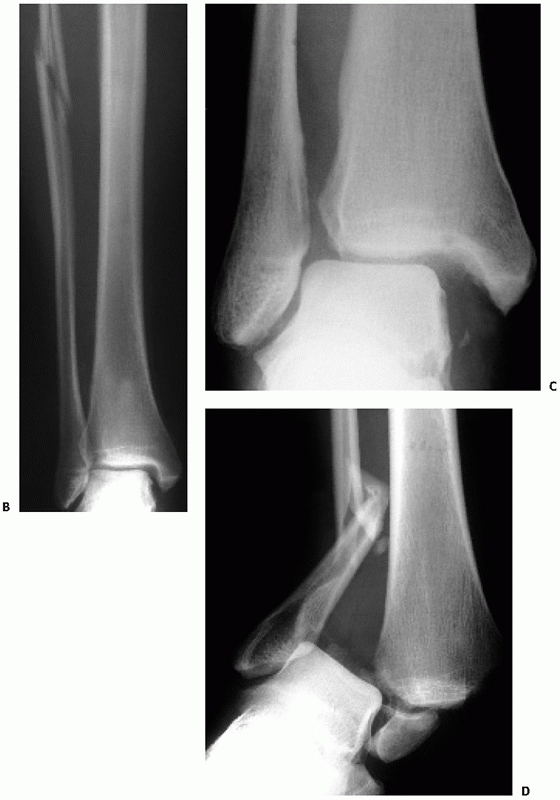

![]() |

FIGURE 57-6 Schematic diagram and case examples of Lauge-Hansen SER and SA ankle fractures. A.

A supinated foot sustains either an external rotation or adduction force and creates the successive stages of injury shown in the diagram. The SER mechanism has four stages of injury, and the SA mechanism has two stages. (continued) |

FIGURE 57-6 (continued) AP (B) and lateral (C)

radiographs show an unstable SER stage IV ankle fracture with the characteristic oblique distal fibula fracture and a medial side injury. D. An AP radiograph of a SA ankle fracture with a transverse fibula fracture and an impacted medial malleolar fracture. |

vertical shear pattern of the medial malleolus fracture is the sine que

non of this injury pattern and may be the only osseous injury with the

FIGURE 57-8 Schematic diagram and case examples of Lauge-Hansen PER and PA ankle fractures. A.

A pronated foot sustains either an external rotation or abduction force and creates the successive stages of injury shown in the diagram. The PER mechanism has four stages of injury, and the PA mechanism has three stages. (continues) |

FIGURE 57-8 (continued) An AP radiograph (B)

of the ankle and tibia and fibula demonstrate a high fibula fracture. External rotation stress shows lateral displacement of the talus and widening of the distal syndesmosis (C). These radiographs are characteristic of a PER rotation injury. D. An AP radiograph of a typical PA ankle fracture. The fibula is laterally comminuted. |